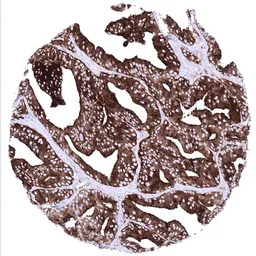

IHC-P analysis of human prostatic adenocarcinoma tissue section using GTX04396 Prostatic Acid Phosphatase antibody [MSVA-452M] HistoMAX.

Prostatic adenocarcinoma (Gleason 448) with strong diffuse Prostatic Acid Phosphatase positivity.